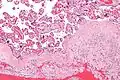

Acute choriodeciduitis, with neutrophils seen in the chorion and decidua.

Acute choriodeciduitis, with neutrophils seen in the chorion and decidua.